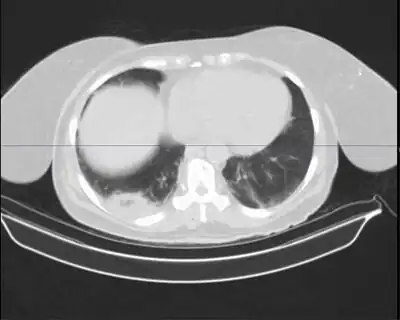

Mycobacterium nebraskense is a slow growing, yellow, pigmented mycobacterium[1] that was first isolated from human sputum at the University of Nebraska Medical Center, in Omaha, Nebraska, USA. Mycobacterium species are common causes of pulmonary infections in both humans and animals.